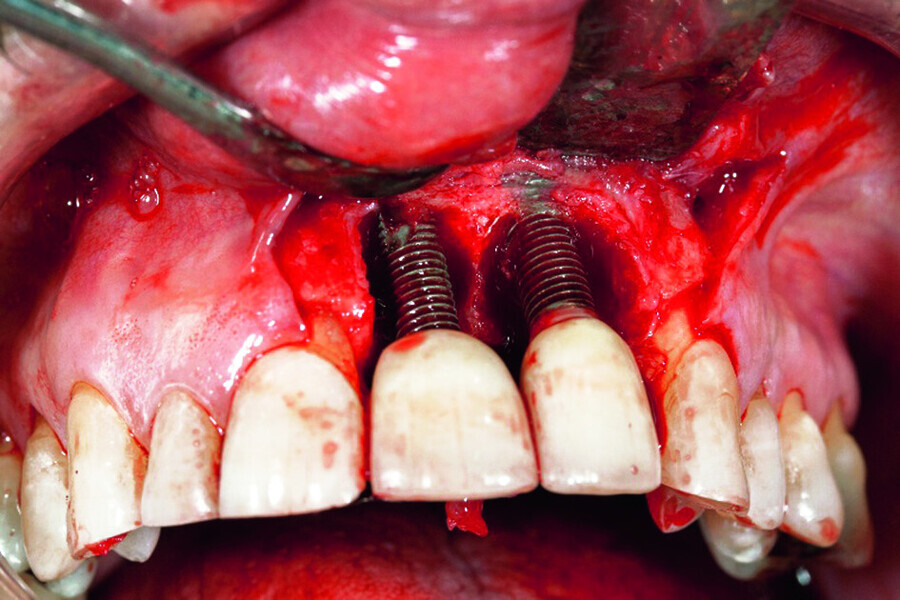

Peri-implantitis therapy